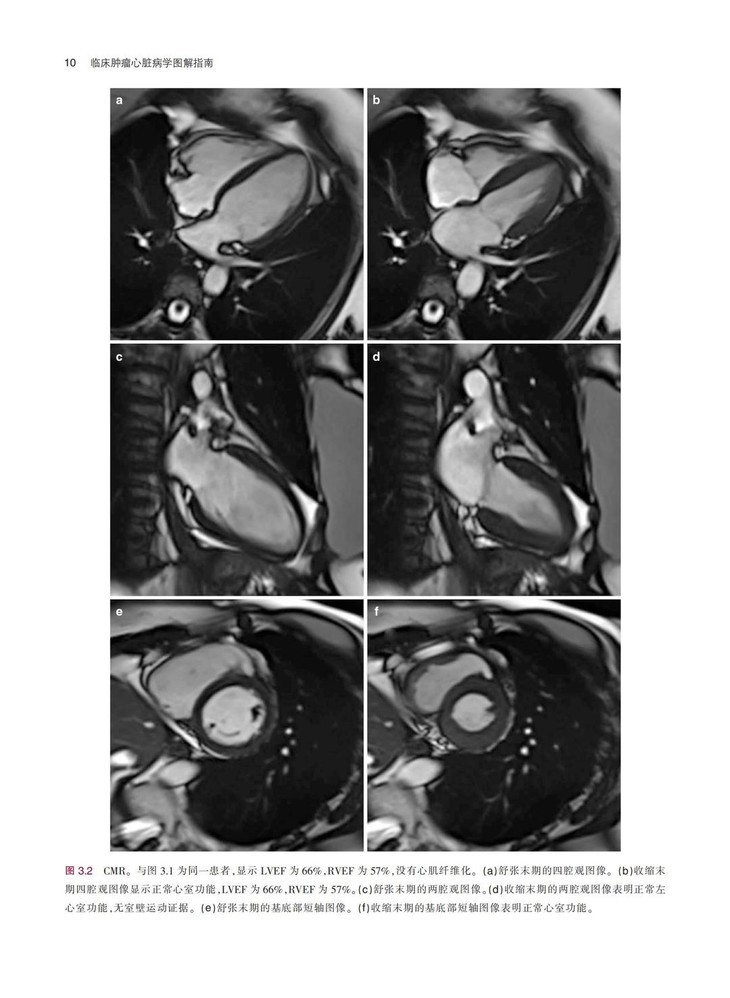

《临床肿瘤心脏病学图解指南》一书结合丰富的临床病例,系统地描述了癌症与心血管领域常见的临床问题,患者主要为既往有心血管疾病的癌症患者,或癌症患者继发复杂心血管疾病,全书对疾病的诊断、检查方式、治疗方式等内容进行了详细阐述,并配有大量的图片,可帮助读者更加清晰地了解相关内容。本书通过结合相关临床病例的方式,在强化理论的同时,突出临床应用特性。本书对我国临床肿瘤心脏病学的基础研究和临床实践有明确的指导意义,对于肿瘤或心血管领域的临床医师及相关研究者具有很强的参考价值。

配有大量手术图片和超声图片,图文并茂,可以为读者提供临床指导,实用性很强